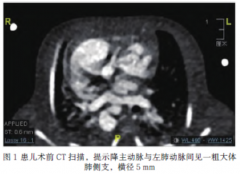

内脏异位综合征患儿围手术期灾难性血流动力学

作者:李星寰,云南省阜外心血管病医院麻醉科;贾爰,中国医学科学院阜外医院麻醉中心 1.病例资料 患儿,男,39天,3....